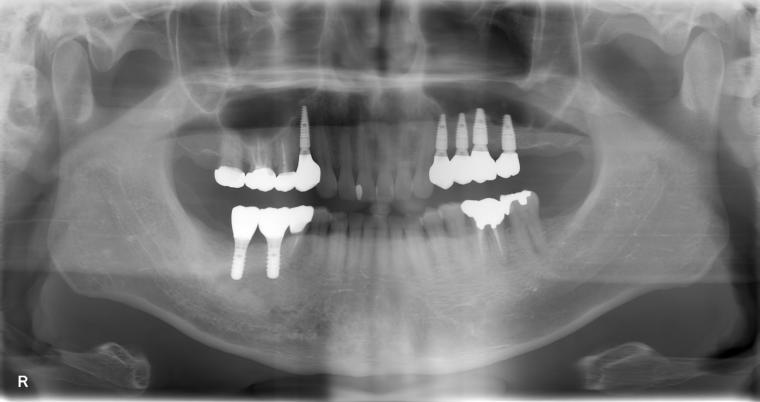

AFTER

41歳男性/上5本欠損/インプラント埋込手術

上5本が虫歯になってしまった為治療をすることになった患者さんです。

虫歯が進行していて、歯を保存出来なかったため歯を抜いて人工の骨を足してからインプラントを

5本埋込した患者さんです。

現在も定期検診で拝見させていただいてます。